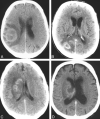

CNS lymphoma consists of 2 major subtypes: secondary CNS involvement by systemic lymphoma and PCNSL. Contrast-enhanced MR imaging is the method of choice for detecting CNS lymphoma. In leptomeningeal CNS lymphoma, representing two-thirds of secondary CNS lymphomas, imaging typically shows leptomeningeal, subependymal, dural, or cranial nerve enhancement. Single or multiple periventricular and/or superficial contrast-enhancing lesions are characteristic of parenchymal CNS lymphoma, representing one-third of secondary CNS lymphomas and almost 100% of PCNSLs. New CT and MR imaging techniques and metabolic imaging have demonstrated characteristic findings in CNS lymphoma, aiding in its differentiation from other CNS lesions. Advanced imaging techniques may, in the future, substantially improve the diagnostic accuracy of imaging, ultimately facilitating a noninvasive method of diagnosis. Furthermore, these imaging techniques may play a pivotal role in planning targeted therapies, prognostication, and monitoring treatment response.